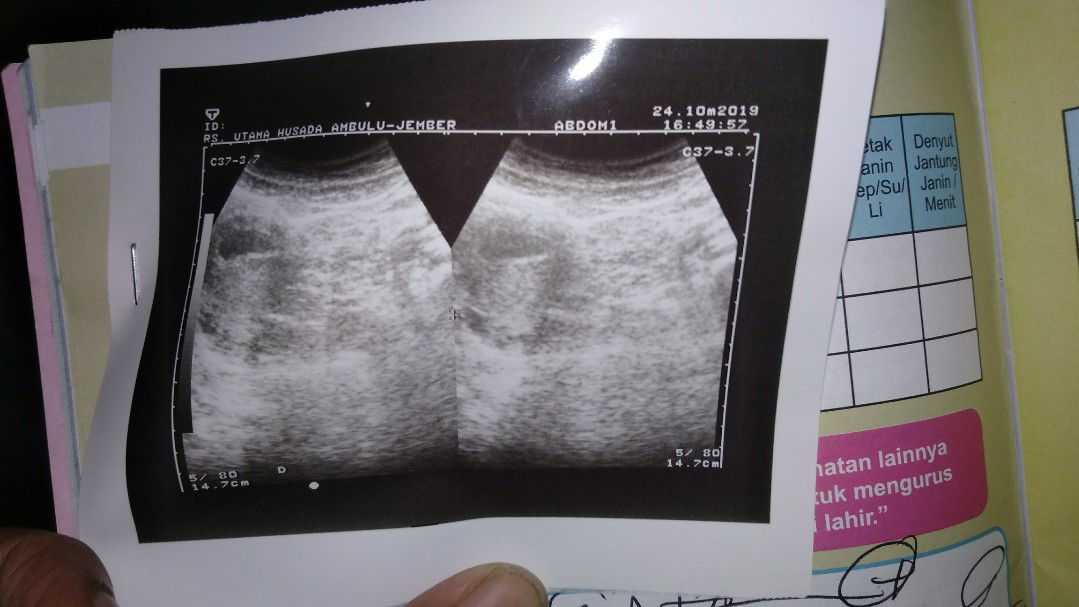

usia kehamilanx brp minggu pd foto hsil usg?

Bunda2 mau tx yg sdh berpnglman kira2 usia kehmilanx brpa minggu ya soalx kmrin dokterx gk jelas dan kburu2 hx bilng sehat dan bgus rahimx trus perwtx jg jlsinx gk terlalu detailll

Usia GA : .... ada tulisannya gt klo emg di fotonya ada